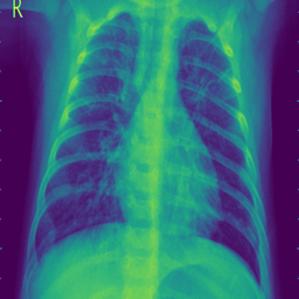

These steps collectively enhance the critical features of the CXR images, aiding in more accurate analysis. Figure2 shows the comparison between CXR images before and after preprocessing highlighting the enhanced clarity and feature extraction achieved through the applied filters.

Figure 2: Comparison of CXR Images Before and After Preprocessing